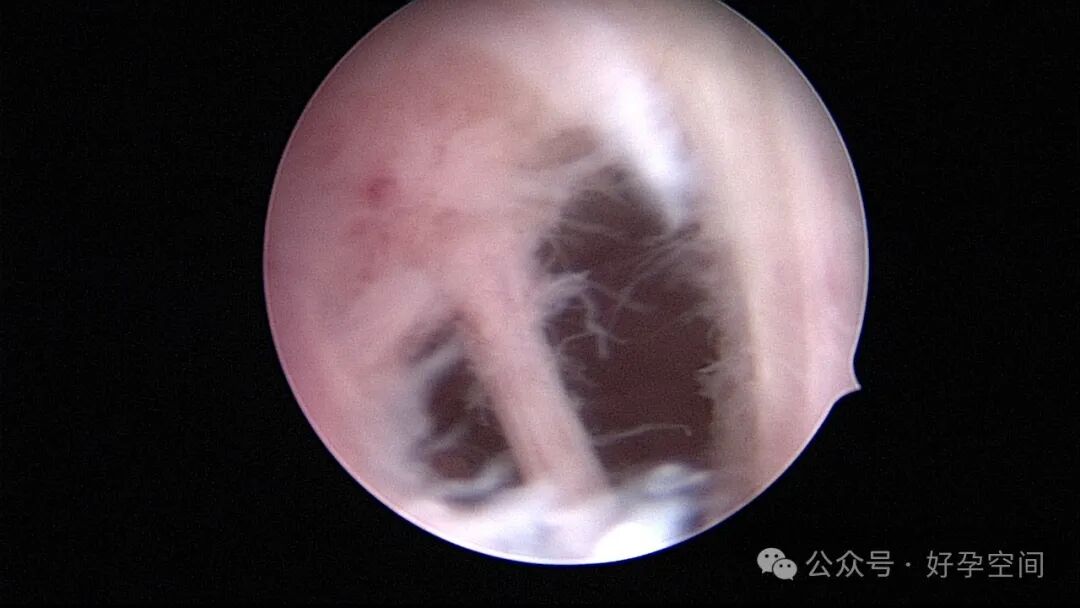

病例2:32岁,G3P1,剖宫产1次,本次停经60+天,稽留流产,宫腔镜辅助下清宫,宫腔广泛粘连,单极电针分粘。术后19天宫腔镜二探,宫腔后壁见1.0cm*1.0cm组织凸起,宫腔镜电切送病检,病检结果为宫腔增殖期样子宫内膜,另见血凝块及纤维素样坏死组织,浅肌层内可见少许滋养叶细胞(病理医生曾与临床医生沟通,病理图片跟超常胎盘部位反应很相似,但最后仅给出了以上病检诊断)。